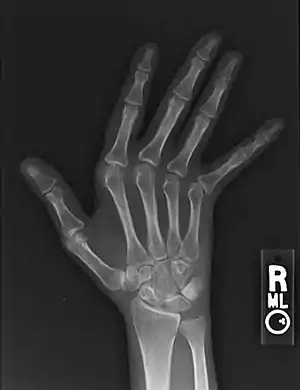

| Jaccoud arthropathy seen on a hand x-ray. As opposed to arthropathy due to rheumatoid arthritis, there are no erosions. | |

Plain radiograph hand radiographs typically show marked ulnar subluxation and deviation at the metacarpophalangeal joints. -absence of erosions is a notable feature, although occasionally "hook" erosions may be observed, which are similar to those seen in SLE and ankylosing spondylitis . -evidence of muscle (soft tissue) atrophy also may be present